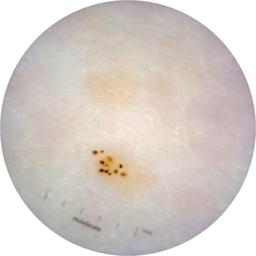

ISIC_6363669

MEL-SELF Trial, https://www.sydney.edu.au/medicine-health/our-research/research-centres/melself-project.html

Clinical

Field Value

acquisition_day 264

age_approx 65

anatom_site_1 Trunk

anatom_site_2 Anterior trunk

anatom_site_general anterior torso

concomitant_biopsy False

diagnosis_1 Benign

diagnosis_confirm_type single image expert consensus

family_hx_mm True

image_manipulation instrument only

image_type dermoscopic

lesion_id IL_2591344

patient_id IP_1322385

personal_hx_mm True

sex female